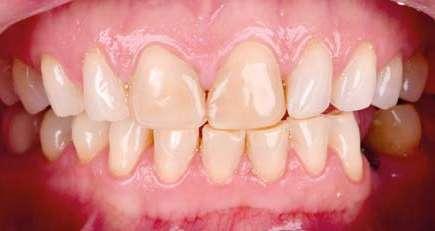

Presentación del caso clínico

A continuación, presentamos el caso clínico de una paciente con unos dientes mal posicionados y con una coloración acentuada sobre todo a nivel de los centrales que además presentaban extensas restauraciones antiguas de composite en interproximal cerrando diastemas que originalmente presentaba la paciente. Estos dientes necesitarán tener una preparación un poco más subgingival y también removido previamente todo el composite antiguo con el objetivo de camuflar este cambio de color y evitar zonas visiblemente no estéticas.

Además, lo combinaremos con unas carillas inyectadas inferiores también planificadas digitalmente y sin tallado, para crear una armonía y equilibrio con la parte superior.

1 Inicio.

Como podemos observar la paciente tenía un sustrato muy desfavorable, con un color aproximado de A3,5 Vita.

Para la arcada inferior se optó por unas carillas inyectadas, completamente respetuosas con los tejidos, que nos permiten mejorar la apariencia de los dientes y dar así una mayor armonía con la parte superior. Al ser también planificadas digitalmente aseguramos que lo que colocamos en boca sea una fiel reproducción del diseño previamente aceptado por el paciente y el profesional.

Mockup.

En la arcada superior por el contrario se decidió poner unas carillas de disilicato para poder cubrir las expectativas de la paciente y ajustar el color al que ella deseaba, bajando casi en 5 tonos el color final. Se planificaron preparaciones digitales conservadoras.

La tecnología digital permite lograr el equilibrio de espesores ideal para cada caso, así como un eje de inserción adecuado. Todo esto permite dar una garantía de longevidad a las restauraciones planificadas.

En este caso se realizó una preparación previa a la preparación guiada en los márgenes y zonas interproximales, para camuflar el sustrato y dar una correcta inserción; y posteriormente se utilizaron unas guías de tallado diseñadas digitalmente para obtener los resultados precisos y predecibles que requería el caso.

La preparación previa junto a la preparación guiada, resultaron en un equilibrio ideal para los espesores mínimos que requería el caso. Se realizó una prueba en seco para valorar el ajuste final de las restauraciones.

Para cementar las carillas y evitar movimientos no controlados y una incorrecta cementación, utilizaremos una guía de posicionamiento simultáneo, esta guía no es de cementación en bloque ya que las carillas están perfectamente individualizadas. Únicamente sirven para llevar a la boca del paciente las carillas y cementarlas de una forma 100% segura, evitando el estrés que genera un posible movimiento durante la cementación y acelerando los tiempos de trabajo.

Consiguiendo así una perfecta adaptación de los márgenes de las restauraciones y la sensación de naturalidad e integración que se observa en la imagen final.

Como se puede observar en la imagen comparativa, la planificación se reproduce de una forma fiel a lo que se había planificado y aceptado por la paciente. Por tanto, no es una técnica susceptible al operador, que se realiza controlando mucho mejor los tiempos y los resultados obtenidos.

15 16 17 18 19 20 21 Preparación. Prueba en seco. Ajuste. Final.

¡Obteniendo un caso espectacular en apenas un par de citas!

Y pudiendo, gracias al uso de este tipo de tecnología, controlar las expectativas y resultados desde el principio hasta el final del caso.

El momento más esperado es el de la celebración por parte de la paciente y del equipo, al conseguir el resultado exacto que se había prometido al principio por medio del mockup y que determinará la confianza que nuestros pacientes depositarán en nosotros cuando les planteemos este tipo de tratamientos. 